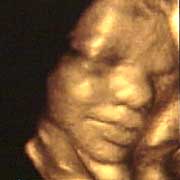

圖文:胎兒子宮內(nèi)表情豐富 專家稱提供研究新依據(jù)

中新網(wǎng)9月13日電 英國天空新聞報道,英國科學家圖亞特·坎貝爾最近利用先進的掃描技術清晰地拍下了孕婦子宮中胎兒的表情,透過他拍攝的照片,人們可以清楚的看到一個尚未降臨世間的小生命喜、怒、哀、樂的表情。

斯圖亞特.坎貝爾是倫敦著名的產(chǎn)科教授,他利用超聲掃描技術拍攝到了胎兒在子宮中打呵欠、眨眼、吮手指、哭泣甚至微笑的畫面,這些都為胎兒行為的研究提供了新的依據(jù),專家認為,這一突破將推動嬰兒健康科學的發(fā)展,包括對唐氏綜合癥等嬰幼兒疾病的診治將起到極大的推動作用。